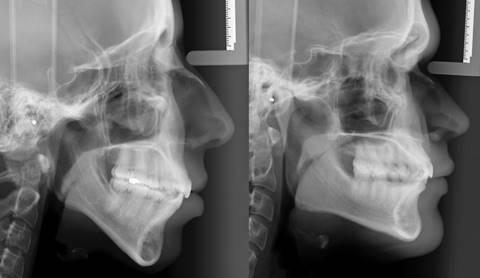

Se confeccionó una guía visual (Fig. 1) con 8 características faciales basadas en las observaciones de Jarabak y Fizzell7, debido a su facilidad para reconocerlas en la telerradiografía. Se entregó a 69 estudiantes de quinto año de la Facultad de Odontología de la Universidad de Chile sin formación previa en cefalometría. Los alumnos tuvieron diez minutos para estudiar el documento, luego se proyectaron dos telerradiografías donde se apreciaban los siguientes ítems a evaluar (Fig. 2):

Los participantes asignaron un puntaje de 1 a 5, donde 1 correspondía a una característica braquifacial marcada y 5 a una característica dolicofacial acentuada.

Al analizar la dificultad de los ítems (Gráfico 1), se observa que los ítems Divergencia facial, Proyección del mentón, y Ancho de la rama mandibular se clasifican con dificultad “fácil o muy fácil” (Logit < -1); los ítems Escotadura sigmoídea y Relación de la rama y cuerpo mandibular se clasifican con dificultad “adecuada” (Logit entre -1 y +1); los ítems Cóndilo/Coronoides, Ángulo goniaco y Escotadura antegonial se clasifican con dificultad “difícil o muy difícil” (Logit > +1).

En este estudio los ítems Proyección del mentón, Divergencia facial y Ancho de la rama mandibular obtuvieron un puntaje (Logit) menor a -1, por lo que fueron clasificados como fáciles o muy fáciles. De ello se desprende que los estudiantes de 5to año son capaces de visualizar sin problemas esas estructuras en la telerradiografía con solo 10 minutos de entrenamiento, por lo que se podría construir una escala basada en estos parámetros.

Por otro lado, los ítems Relación de altura del cóndilo y coronoides, Ángulo goniaco y Escotadura antegonial, obtuvieron un puntaje (Logit) mayor a -1, por lo que se clasificaron con dificultad difícil o muy difícil. Si bien los ortodoncistas y cirujanos podrían identificar fácilmente todas las características, las más difíciles no deberían ser tomadas en cuenta para desarrollar una escala de identificación cualitativa del biotipo facial orientada a odontólogos generales.

Se determinó que los parámetros Relación entre la rama y el cuerpo mandibular, Proyección del mentón, Divergencia facial, Ancho de la rama mandibular y Escotadura sigmoidea son fáciles de visualizar en la telerradiografía de perfil, y por tanto útiles para evaluar el biotipo facial de manera sencilla y rápida